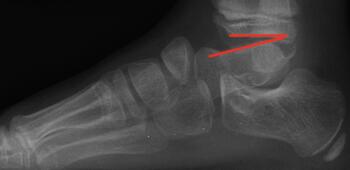

As the Ponseti grew in popularity, I noted significant discrediting of surgical options. Well long-term studies on the Ponsetti are starting to surface, and it is not without its own problems. Kids are lost to follow-up, not braced appropriately, and just like we saw in long-term studies with the posteromedial release, there is a lot of undercorrection. Casting cannot and will not ever achieve what the Cincinnati release can. Although the Ponseti may not have the complications of the Cincinnati, X-ray data reveals that the Ponseti cannot and does not correct everything, most critically, talocalcaneal angles. You can not solve a clubfoot with an Achilles tenotomy and an overly aggressive casting. As these kids develop, I see residual met adductus and calcaneal varus, along with casting complications like flat top talus and met primus elevatus. I then see that they will develop DJD just like posteriomedial and Cincinnati releases. Haasbeck and team in 1997 reported that the Cincinnatti required fewer procedures than the posteromedial release over the life of their study.14 Thomas performed a systematic review in 2019, concluding that the longer the study follow-up, the greater the relapse rate and the poorer the results of the Ponseti.15 For most of us who have done clubfeet surgery for many years, this is no surprise. Among the 46 studies meeting inclusion criteria, they saw as high as 67 percent required future surgeries to address relapse.15

Here is a typical case presentation. A 21-year-old Marine at Ft. Leonard Wood for training underwent a Cincinnati release at one year old and had stellar follow-up. Her surgeon even wrote her medical waiver for entrance into the Marines. She ran track in high school. She finished boot camp and completed all of her Marine training, but now has chronic pain. She no longer can run. She hasn’t passed her physical training in over a year. She developed talonavicular DJD. By all accounts, her overall clubfoot should be rated an A+; no residual deformity, normal talocalcaneal angles on AP and lateral views, no equinus, no residual varus, only slight met primus elevatus, but no signs of a flattop talus. Clinically, she lacks subtalar range of motion, which I commonly find post-clubfoot release of any kind. So many in the military do very well for a while, but the demands of the military eventually catch up to them. We all root for clubfeet to make it, but the odds are stacked against them.